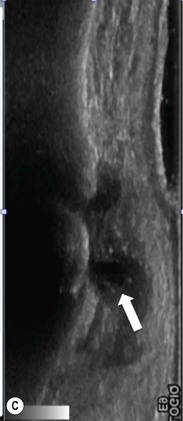

Ischiofemoral impingement is a recently described condition predominantly affecting women associated with narrowing of the space between the ischial tuberosity and lesser trochanter of the femur. It is thought that the quadratus femoris muscle which passes through this space may be impinged during repetitive hip movement, giving rise to pain. MRI reveals narrowing of the space associated with oedema of the quadratus femoris muscle belly and adjacent free fluid (Fig. 46-40).26 However, similar appearances may be found in asymptomatic individuals and the clinical significance of this has not yet been established.